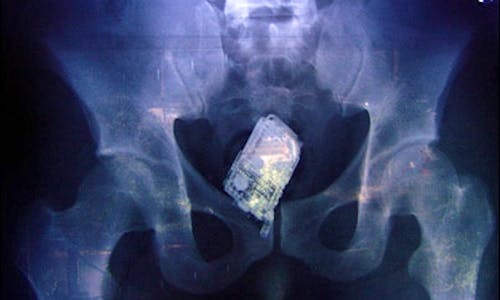

American prisons suffering cell phone smuggling explosion.

Nearly 1,400 cell phones were seized from California state prisons in 2007 according to a story published on KCRA.com That number has now increased more…